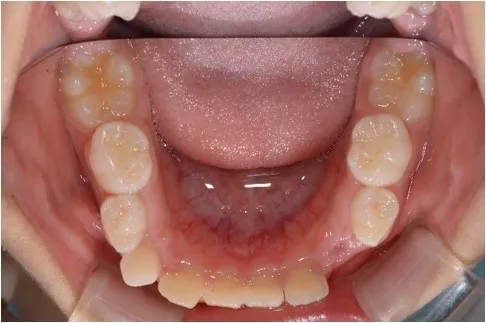

【治療前 下顎】

【治療開始から1年後 下顎】